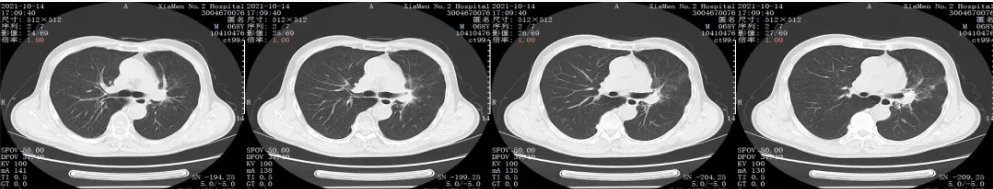

胸部CT平扫+增强:2021年10月复查

胸部CT平扫+增强:用药31个周期后复查

疗效评价:SD

胸部CT平扫+增强:2024年复查

后续治疗:目前共进行了50周期的免疫治疗,病情稳定,建议给予停用

胸部CT平扫+增强:2025年2月20日末次用药,停用4月后复查

疗效评价:SD(近期于2025年6月16日复查CT,复查结果显示病情稳定)